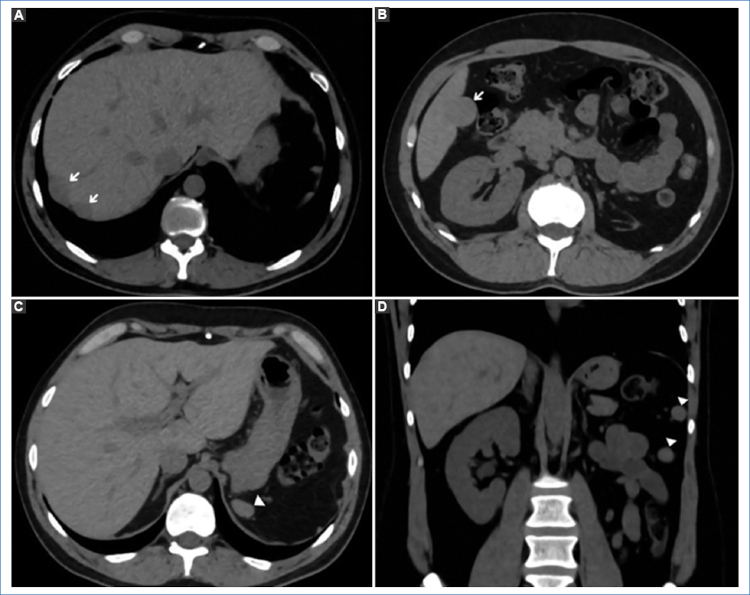

Presentamos el caso de un hombre de 43 años con antecedentes de nefrectomía izquierda y esplenectomía como consecuencia de un trauma cerrado de abdomen por accidente de tránsito, que consulta para caracterización de lesiones hepáticas. Presenta tomografías computadas (TC) previas no contrastadas de control y posteriores a la cirugía, en las que se observaban a nivel peritoneal múltiples imágenes nodulares en el flanco izquierdo y subdiafragmáticas bilaterales; las ubicadas a nivel subdiafragmático derecho se encontraban en íntima relación con la cápsula hepática, cercanas a los segmentos VII y VIII, y persistieron sin cambios en los sucesivos estudios (Fig. 1).

En los estudios de TC multidetector y RM, el tejido esplénico heterotópico tiene la misma apariencia e igual comportamiento que el bazo tras la administración del contraste endovenoso. En la TC sin contraste, la lesión es isodensa con respecto al parénquima hepático y presenta realce en fase arterial, difícil de diferenciar de un adenoma o un hepatocarcinoma4. En la RM, previo a la administración de contraste paramagnético, la lesión es homogéneamente hipointensa en las secuencias ponderadas en T1 e hiperintensas en las ponderadas en T2; después de la administración del gadolinio es hiperintensa en comparación con el resto del parénquima hepático1,5.